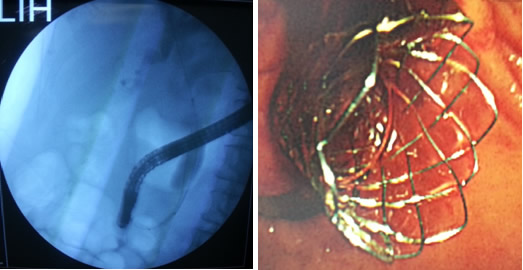

2013年9月份开始,由我院消化内科丁健副主任医师牵头,开展ERCP下乳头括约肌切开取石术和胆总管支架植入术等业务,目前已成功完成病例17例。接受治疗的患者疗效显著,并发症少、住院时间短,取得了良好的社会效益。

ERCP相关诊疗技术是现代胆胰病学的重要组成部分,代表了现代微创手术理念的发展趋向,有着广泛的应用前景,值得大力发展和推广,消化内科为此专门组建了一个医疗小组,为高质量、安全开展ERCP保驾护航。